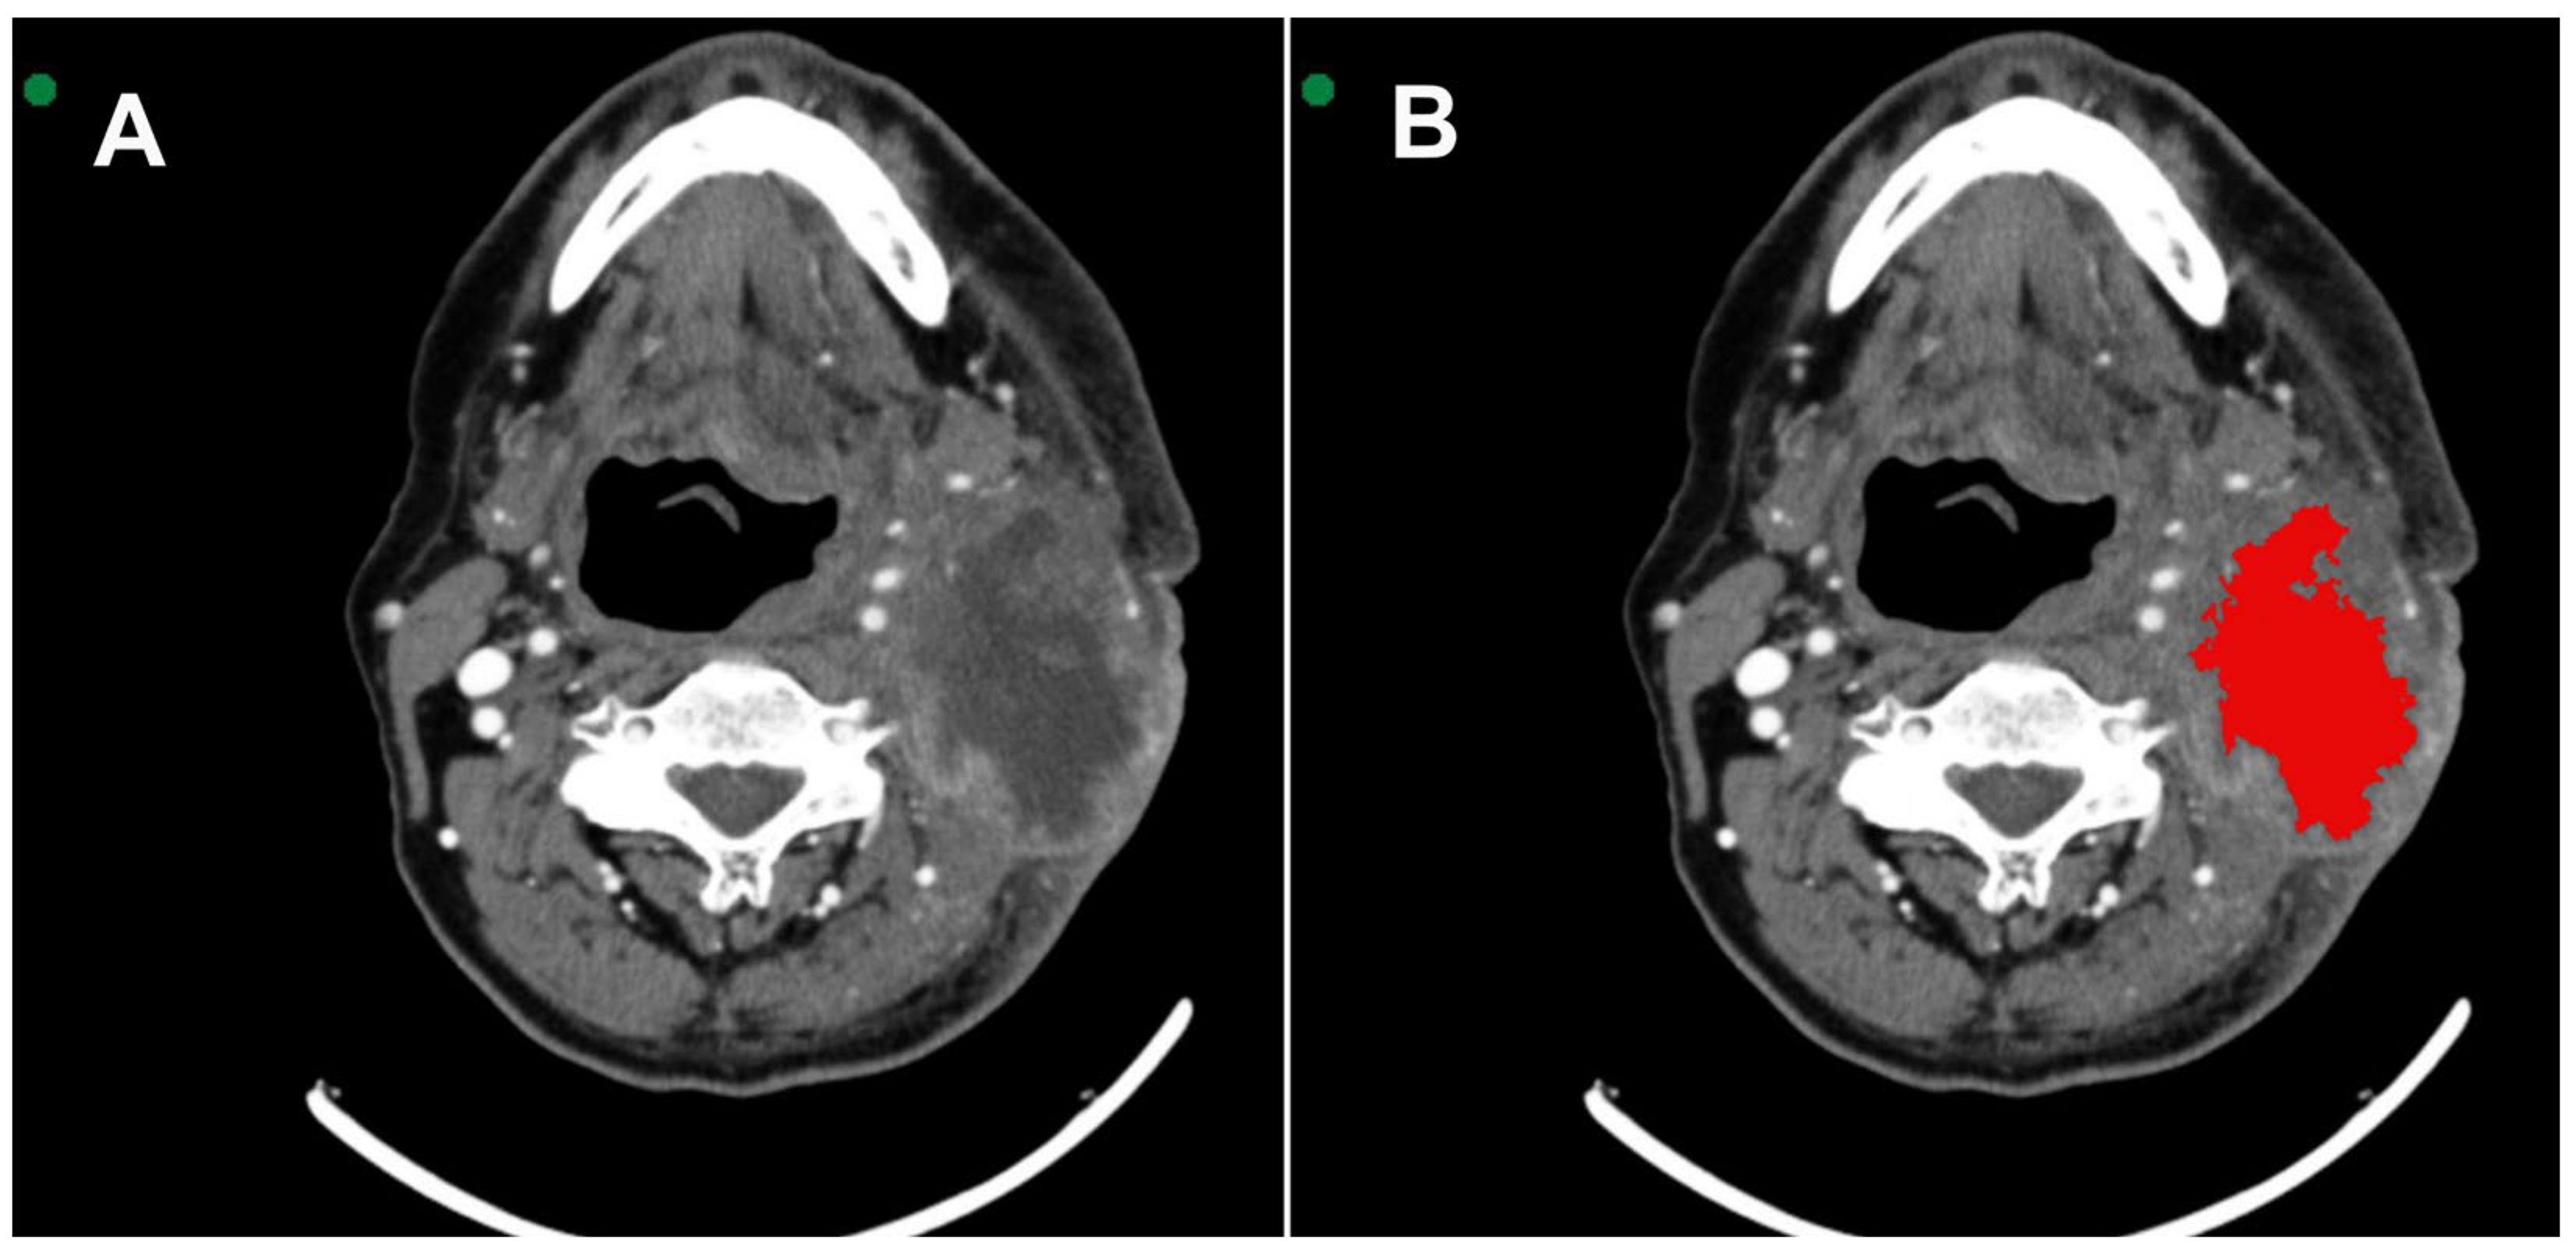

All images were acquired in Digital Imaging and Communications in Medicine (DICOM). MSCT scans were selected based on the identification of the largest area of the lesion. Two radiologists with 6 and 16 years of experience in interpreting MSCT scans were extensively involved in reviewing all the cases. They performed the segmentation with mutual agreement. The InVesalius® software (www.cti.gov.br/invesalius, accessed on 5 July 2023) was used for the initial image processing. Once all the lesions were segmented and similar areas identified, the DICOM files were converted into the NIfTI format by using the InVesalius® software toolbox [21]. Figure 1 shows the segmentation process before calculating the texture parameter values.

Figure 1.

(A) Axial MSCT image shows squamous cell carcinoma located in the tonsillar pillar on the left side. (B) 3D VOI (red) segmentation process covering the lesion.